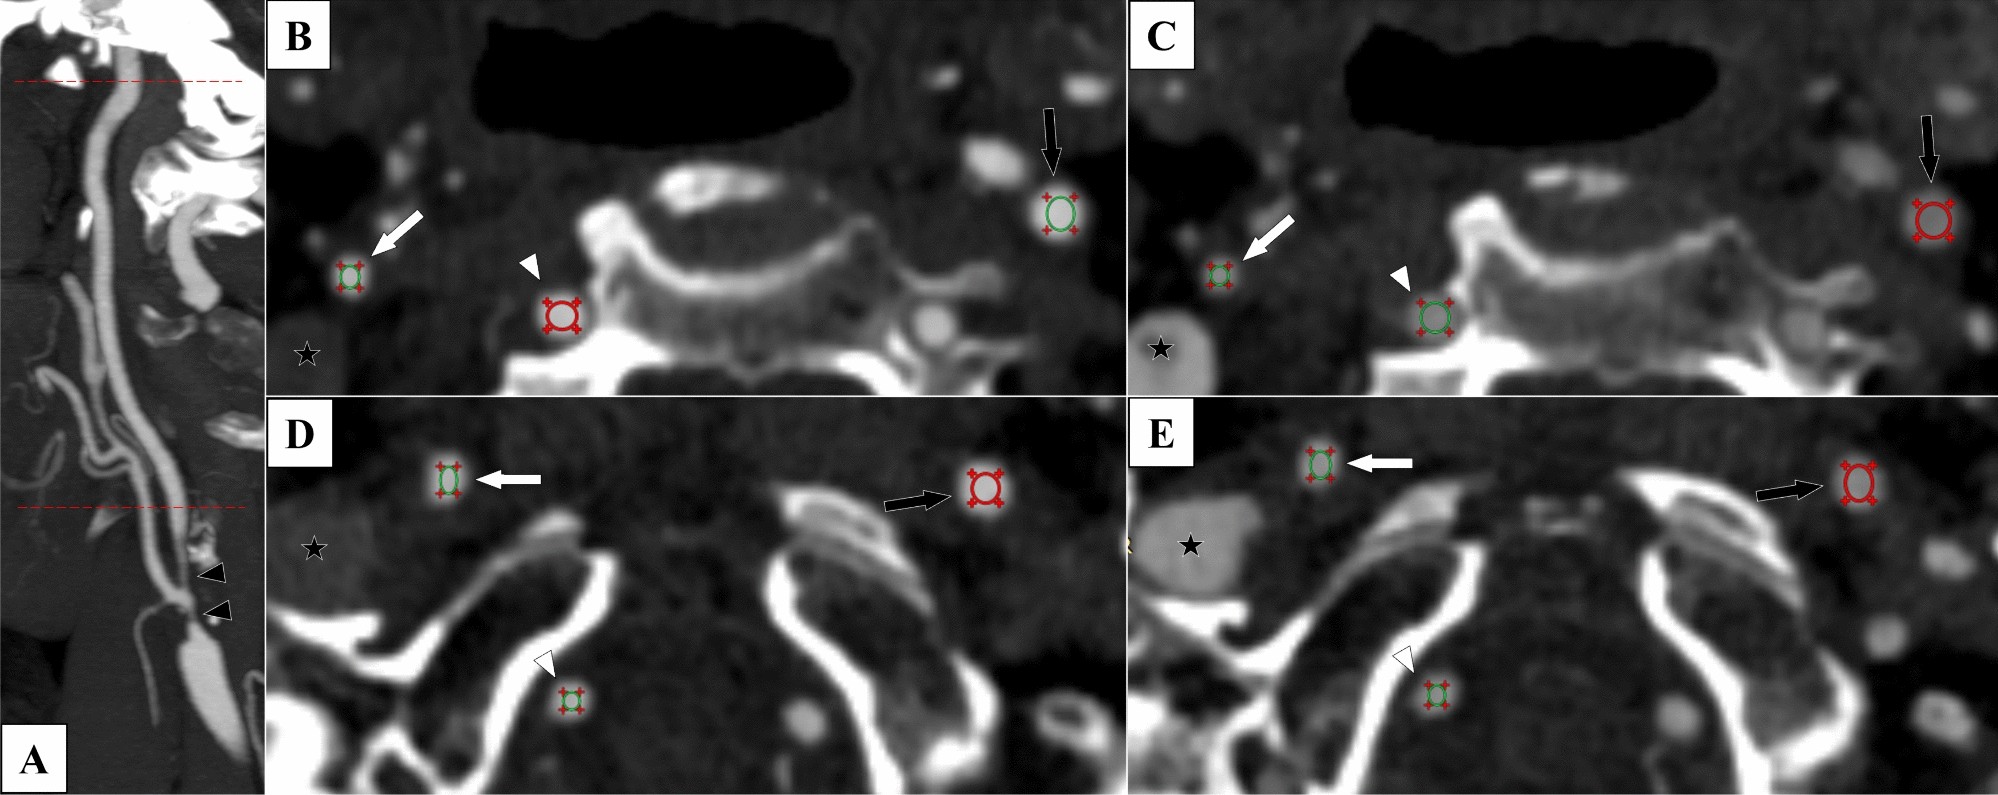

Figure 1

The 12 measurement points in biphasic CTA exams. Case with right-sided near-occlusion without full collapse. 7 s between arterial and venous phase. ROIs placed to avoid the fuzzy edge around the artery. (A) Sagittal view with cervical levels (proximal and distal) marked with red dotted lines. Note that the proximal measurement still refers to the artery beyond (distal to) the stenosis (black arrowheads). (B) Arterial phase, proximal level. 488, 542 and 535 HU in right ICA (white arrow), left ICA (black arrow) and vertebral (white arrowhead). (C) Venous phase, proximal level. 351, 274 and 332 HU. Note the filling of the right jugular vein (black star with white rim). (D) Distal level, arterial phase. 486, 521 and 477 HU. Note the non-intuitive change in vertebral HU between proximal and distal phase that shifts the direction of v-correction from − 47 to + 9 HU whereas c-correction is more intuitive (− 54 and − 38 HU). (E) Distal level, venous phase. 379, 343 and 386 HU.